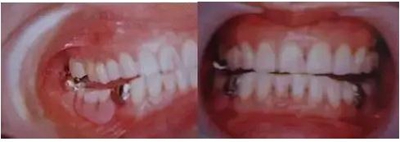

A. 高度減少

作為因正常后方磨牙部咬合支撐喪失引發(fā)的下頜過(guò)閉口咬合,磨牙處部分性發(fā)生的情況稱(chēng)為后牙咬合崩塌(posterior bite collapse)。

磨牙部咬合支撐的喪失是逐漸由殘存的牙齒的牙齒移動(dòng)和不恰當(dāng)?shù)难例X修復(fù)體所引發(fā)的。左右磨牙以及前磨牙完全喪失的情況下,閉口時(shí)沿著上頜前牙舌面傾斜的下頜的前方牙齒接觸的方向,這時(shí)髁狀突非旋轉(zhuǎn)地工作并被施加后方閉口力,導(dǎo)致髁狀突的遠(yuǎn)中和上方變位,會(huì)引發(fā)下頜功能異常的肌肉癥狀。

制作全口義齒的患者情況下,咬合高度設(shè)置低一些會(huì)引發(fā)閉口肌的收縮,有時(shí)會(huì)引發(fā)筋膜疼痛。